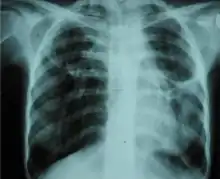

A fibrothorax can typically be diagnosed by taking an appropriate medical history in combination with the use of appropriate imaging techniques such as a plain chest X-ray or CT scan.[3] These imaging techniques can detect fibrothorax and pleural thickening that surround the lungs.[7] The presence of a thickened peel with or without calcification are common features of fibrothorax when imaged.[3] CT scans can more readily differentiate whether pleural thickening is due to extra fat deposition or true pleural thickening than X-rays.[3]

If a fibrothorax is severe, the thickening may restrict the lung on the affected side causing a loss of lung volume.[7] Additionally, the mediastinum may be physically shifted toward the affected side.[3] A reduction in the size of one side of the chest (hemithorax) on an X-ray or CT scan of the chest suggests chronic scarring.[6] Signs of the underlying disease causing the fibrothorax are also occasionally seen on the X-ray.[6] A CT scan may show features similar to those seen on a plain X-ray.[7] Lung function testing typically demonstrates findings consistent with restrictive lung disease.[6]